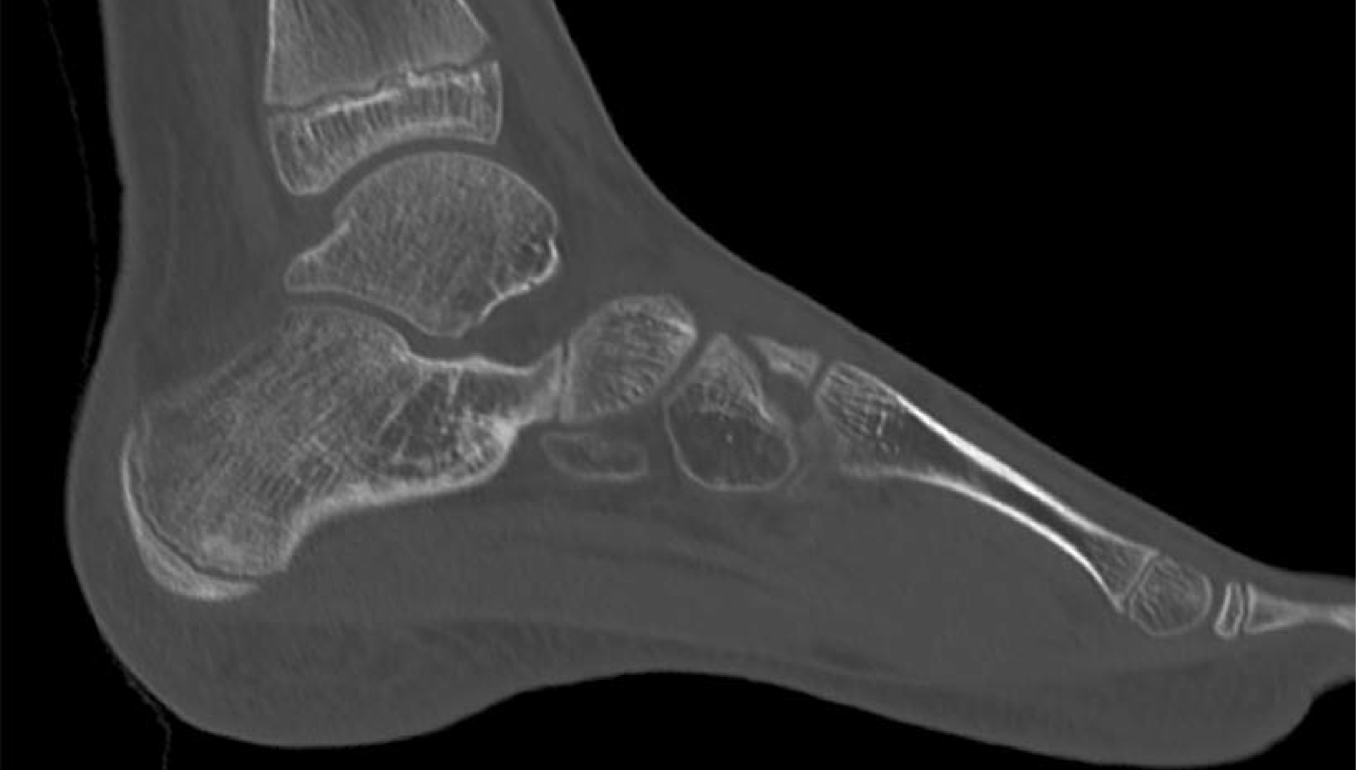

What is the image & view?

Sagittal CT of the foot

What does this “C” sign indicate?

Talocalcaneal coalitions (TCC)

Other than the “C” sign, what is seen radiographically on TCCs?

Talar beaking

What does this “anteater” sign indicate?

Calcaneonavicular coalitions (CNC)